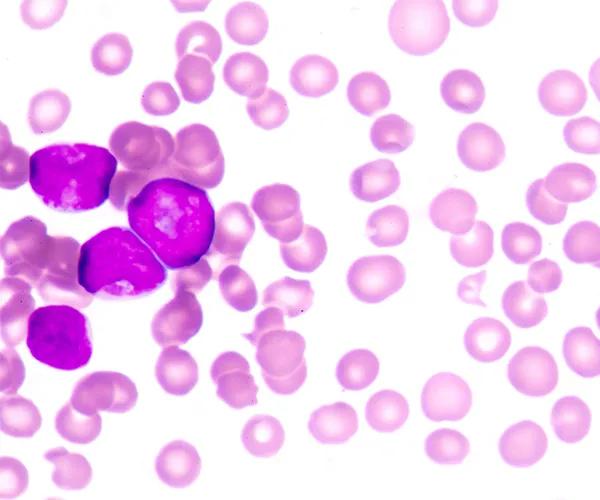

To advance preclinical evaluation of therapies for Acute Myeloid Leukemia (AML), JAX provides a diverse panel of AML Patient-Derived Xenograft (PDX) models that reflect a range of mutational landscapes and treatment backgrounds. Developed from the work of Townsend et al., these models are engrafted into the highly immunodeficient NSG™-SGM3 mouse strain (013062), which offers superior engraftment of human myeloid leukemia cells—making it an ideal platform for testing single agents or combination therapies.